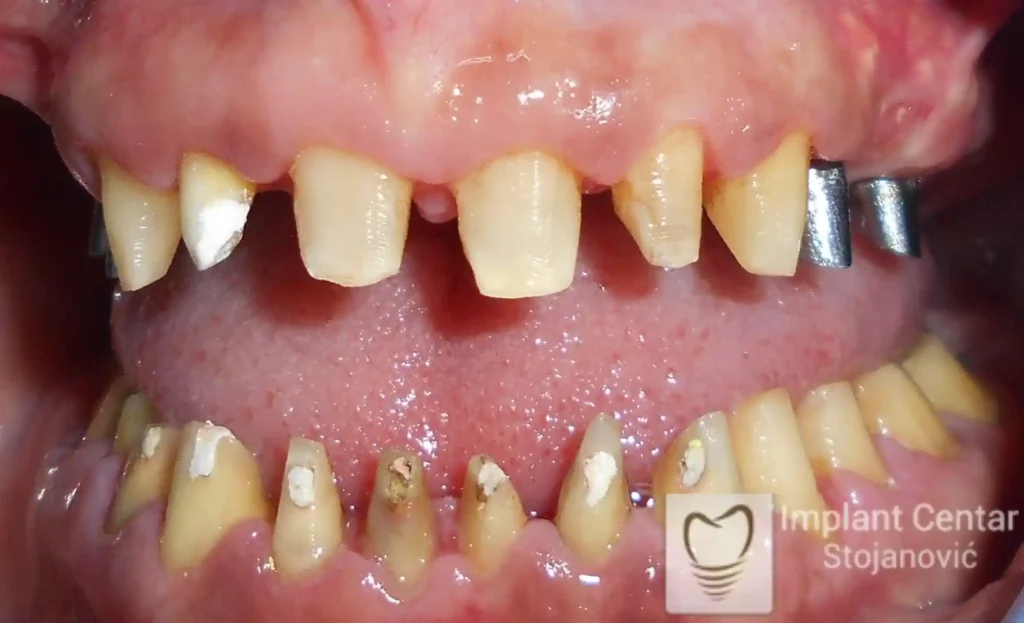

Na slikama 1, 2, 3 , 4  i  5 prikazan je izgled pacijenta pre početka terapije. Nakon detaljne kliničke i radiološke analize, doneta je odluka o vađenju zuba loše biološke vrednosti, dok su bezuba polja sanirana ugradnjom dentalnih implantata.

Nakon ugradnje implantata i pripreme preostalih zuba, pacijentu su izrađene fiksne privremene krunice, čime je postignut eugnatan zagriz već nakon jednog dana (slika 8, 9 i 10). Tokom perioda osteointegracije, pacijent se postepeno privikavao na novi položaj vilica i zagriz.